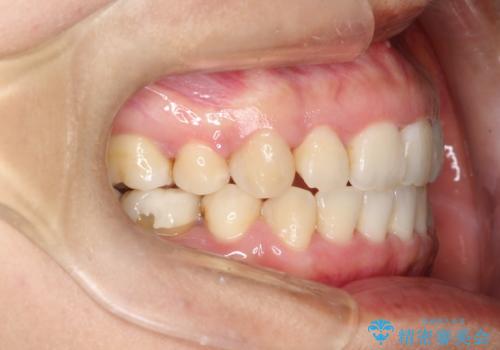

上下の歯のガタガタ ワイヤーでの抜歯矯正で整った歯並びへ

- 上下の歯のガタガタを治したいとのことで来院されました。

がたつきの度合いが強いのと、口元をなるべく引っ込めたい希望がありましたので、ワイヤーでの抜歯矯正となりました。

ガタガタが重度の方は抜歯が必要となることが多いです。

抜歯スペースを使って前歯を引っ込めることにより、口元の突出感も改善できました。